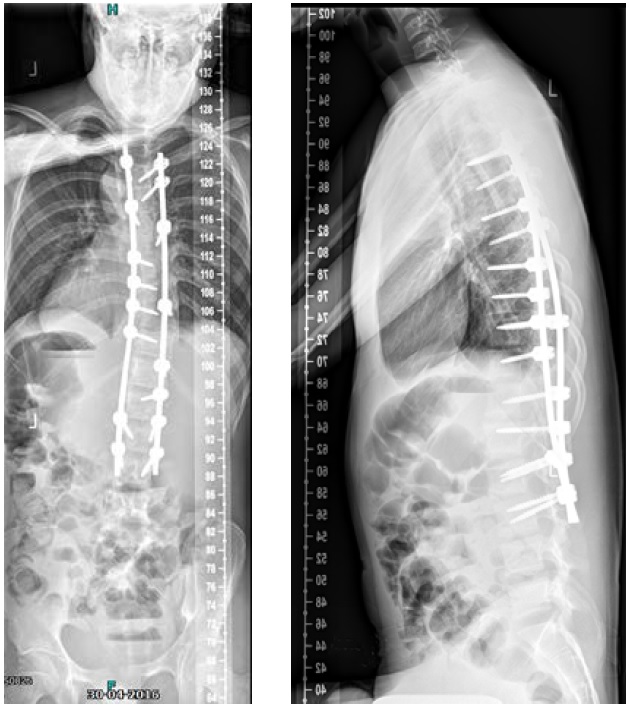

On physical examination a cooperative boy was seen, normal build and height, normal to high paraspinal muscle tone. Standing upright he was off balance to the right. Neurological examination showed absent abdominal skin reflexes bilaterally. The curve was classified as neuromuscular type scoliosis (Fig 6). Due to the curve magnitude, being off balance, and with (severely) limited nonoperative options (Fig 7), surgical treatment was discussed with the family.

He was scheduled for a posterior deformity correction from T4L3. Under general anesthesia, with IONM (TC-MEP) the deformity was corrected. Intraoperatively, an epidural catheter was placed with the tip at T7 for postoperative analgesia.

Mobilisation started the day after surgery. He was discharged the fourth day after surgery. He returned for scheduled follow-up after 7 weeks (Fig 8). He seemed less agitated compared to the period before surgery. He did not seem to have specific limitations.